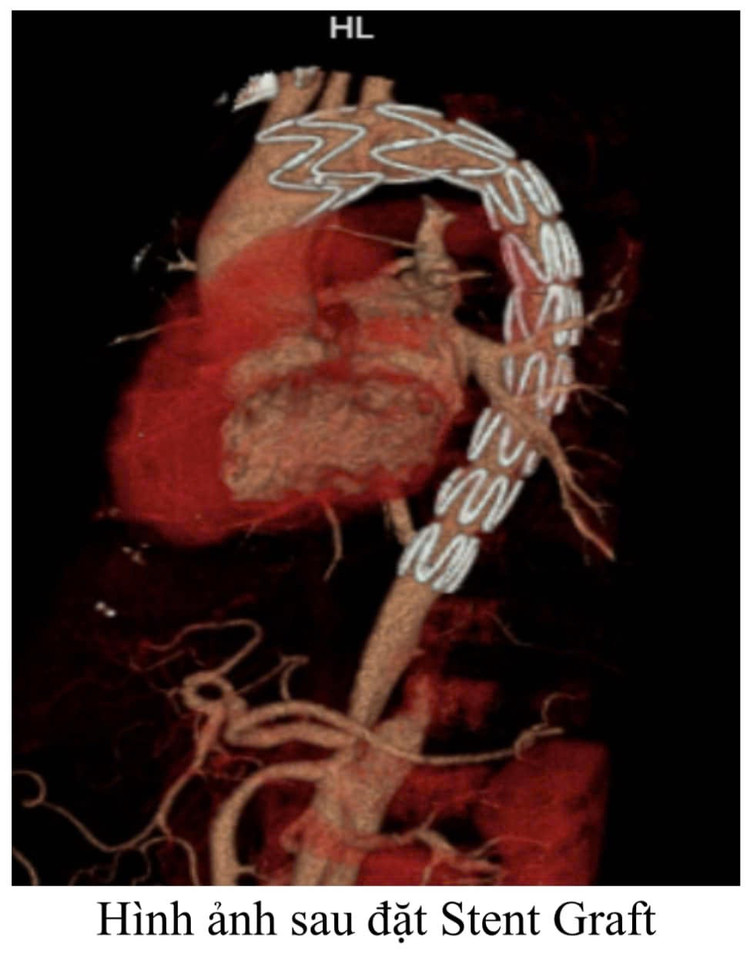

Ngay sau đó, Stent Graft đã được các bác sĩ can thiệp cẩn thận đặt từ ngay phía sau động mạch thân cánh tay đầu xuống động mạch chủ ngực giữ cho động mạch chủ không bị lóc tách, đồng thời nhờ phẫu thuật bắc cầu nối từ trước tưới máu não vẫn được đảm bảo một cách đầy đủ, chỉ cần một vết rạch 2 cm ở vị trí đùi phải, tránh cho bệnh nhân được một cuộc phẫu thuật mở ngực vô cùng nguy hiểm. Sau can thiệp bệnh nhân phục hồi tốt và xuất viện sau 7 ngày điều trị.